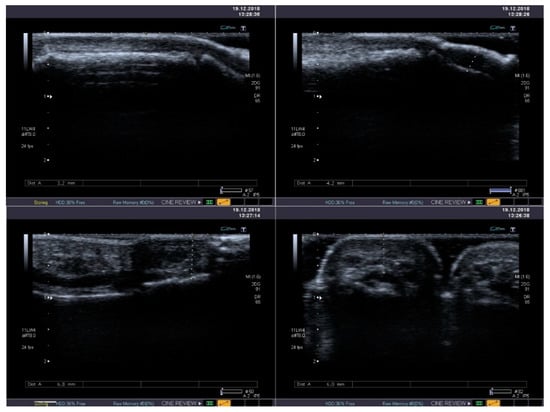

The integumentary system is the most common location of systemic lesions in scleroderma. Thickening and infiltration of the skin is usually present within face and hands (Figure 4). In half of sclerodermic patients with the limited form of the disease usually only the portion distal to the elbow joints is affected, but in the diffuse type the proximal areas are also involved—including the proximal parts of the limbs and the trunk. The advancement of skin lesions is evaluated usually using the modified Rodnan skin score [37]. Moreover, the ultrasound examination allows distinguish edematic lesions from fibrosis, but its reproducibility is relatively low [38]. High-frequency ultrasound offers a potential for objective and quantitative assessment of skin thickness and skin echogenicity in systemic sclerosis (SSc) [39]. It has been shown to be a valid measurement of skin thickening with excellent inter- and intraobserver variability (over 80% for interobserver variability and over 90% for intraobserver variability) [38,40]. High frequency ultrasound might be also useful in evaluation of oral mucosa, where fibrotic lesions are hyperechogenic [41].

Figure 4.

Standard B-mode ultrasound reveals mild thickening and heterogeneous echogenicity of soft tissues with its fibrosis in the thumb (upper panel) and in the second finger (lower panel).

Shear-wave elastography (SWE) was recently proven as a useful method of quantitative skin fibrosis assessment through the evaluation of skin strain. The elastic modulus values are significantly higher in SSc patients than in controls, with very accurate cutoff values, especially for hand fingers localization. Total scores of skin involvement determined at 17 sites (modified Rodnan skin thickness scores) correlate with skin stiffness SWE measurement [42].

SWE is more reproducible and has higher sensitivity than Rodnan Skin Score in the evaluation of skin condition in SSc, especially in case of changes non-detectable on physical evaluation, indicating it might become a useful tool in SSc diagnosis [43].